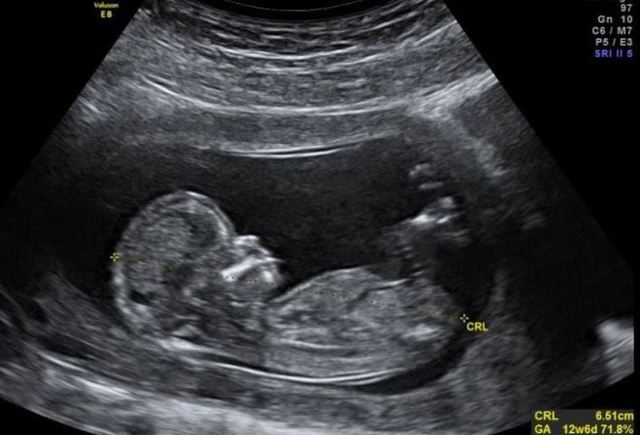

La cabeza es casi la mitad del tamaño total, aparecen los brotes dentarios, ahora pueden cerrar los puños.

Al termino de la semana 12 medirá 7.5cm y pesará 30g, sus ojos están casi completamente desarrollados. Ya se perciben latidos.